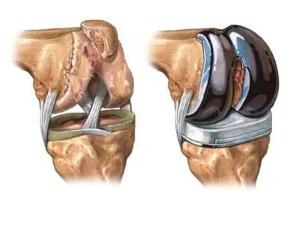

عوارض جراحی مینیسک زانو موضوعی است که بسیاری از بیماران

جراحی ترمیم منیسک زانو یکی از شایعترین عملهای ارتوپدی است

پارگی منیسک زانو یکی از شایعترین آسیبهای زانو است که